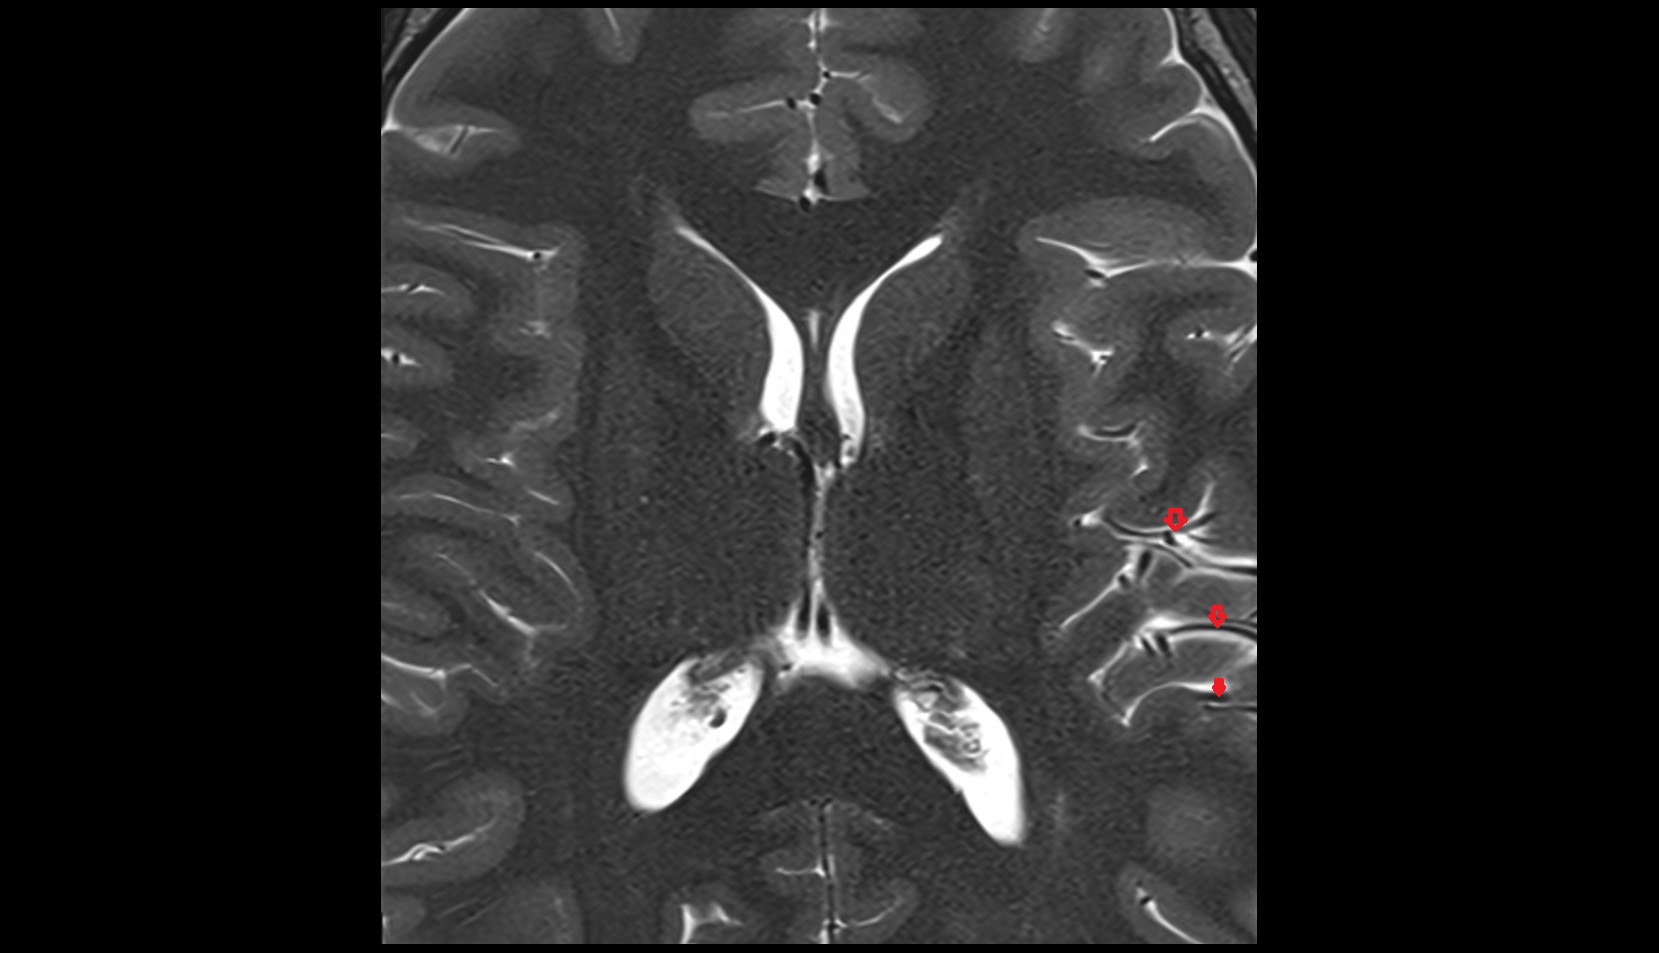

- Atrium of lateral ventricle

- Central part of lateral ventricle

- Frontal horn of lateral ventricle

- Occipital horn of lateral ventricle

- Temporal horn of lateral ventricle

- Third ventricle